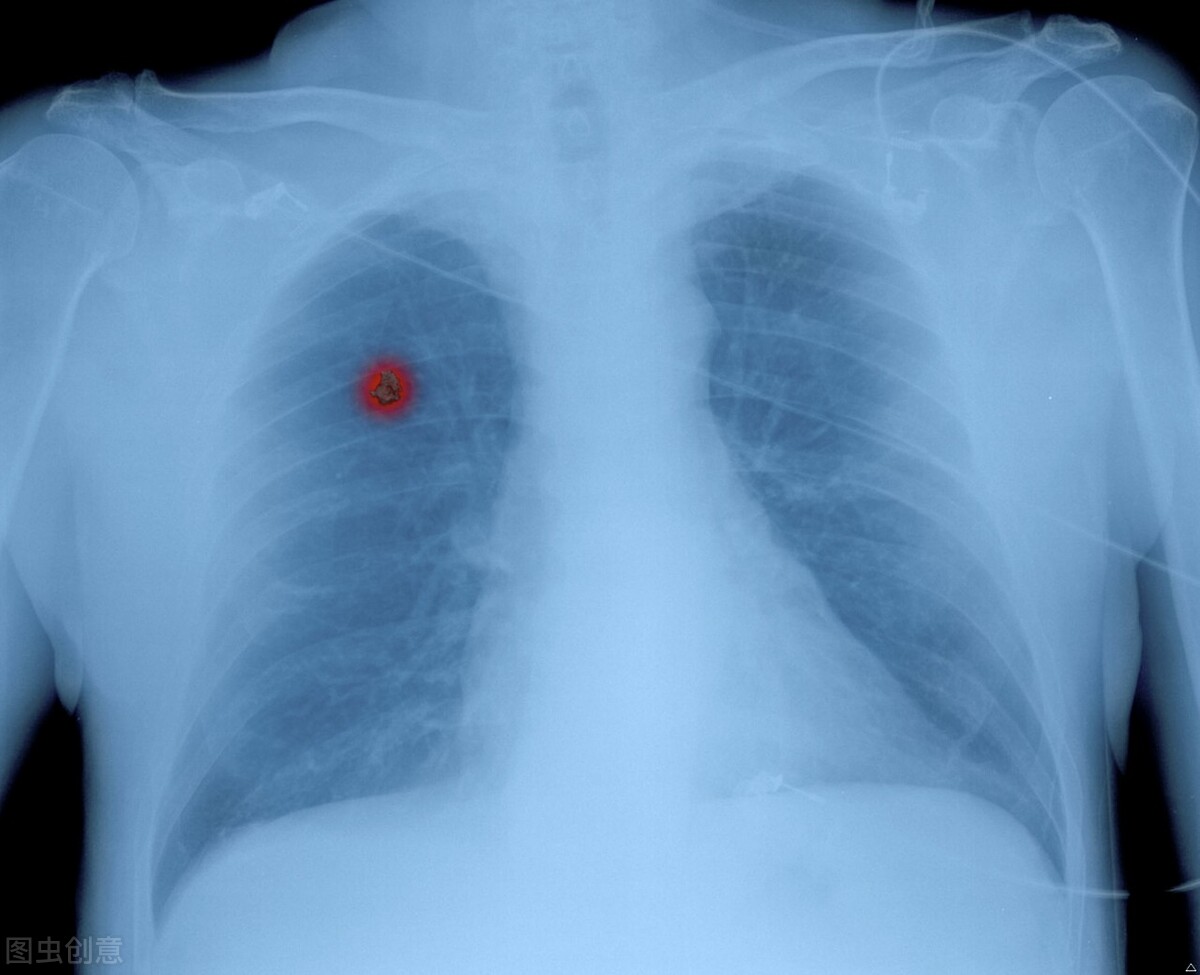

A45精准靶向治疗小细胞肺癌是比较新的一种治疗肺癌的方法,对于小细胞肺癌有很好的治疗的作用,它属于一种精准的靶向性治疗,在彻底清除癌细胞方面的作用是比较好的,同时还不会损伤人体的其他的组织和器官,在激发患者身体免疫力方面也有很好的效果,能够降低转移的概率。